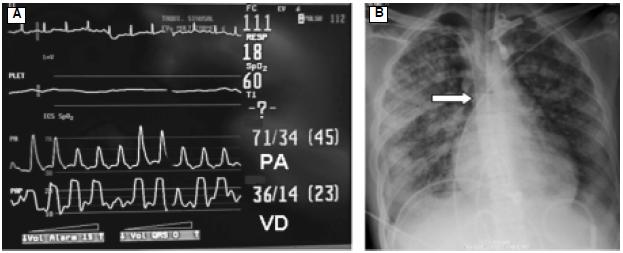

El taponamiento cardiaco es secundario al incremento de la presión intrapericárdica debido al cúmulo de líquido. Las causas más frecuentes de derrame pericárdico son pericarditis, uremia, hipotiroidismo, trauma, cirugía cardiaca y otras enfermedades inflamatorias y no inflamatorias. El objetivo de este artículo es describir el caso de un enfermo con choque séptico que desarrolló taponamiento cardiaco y revisar su patogénesis, diagnóstico clínico y hemodinámico, enfatizando en la importancia de la ecocardiografía como herramienta diagnóstica.

Cardiac tamponade is usually a consequence of increased pericardial pressure with accumulation of pericardial effusion. Pericardial effusion may be caused by acute pericarditis, tumor, uremia, hypothyroidism, trauma, cardiac surgery, or other inflammatory/non inflammatory conditions. In this article we describe a patient with septic shock who developed cardiac tamponade. We review the pathogenesis and clinical and hemodynamic diagnosis of pericardial tamponade, focusing on the diagnostic utility of echocardiography.